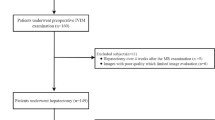

This retrospective study followed the principles of the Declaration of Helsinki and was approved by the Institutional Review Board. Written informed consent was waived. Between 1 March 2014 and 31 July 2017, all patients referred for abdominal MRI for suspected HCC due to chronic hepatitis B virus (HBV) infection were evaluated. Patients were ineligible for inclusion if they (a) had a tumor other than HCC, (b) had undergone previous anti-tumor treatment, (c) underwent hepatectomy at > 1 month after the MRI examination, (d) had simultaneous hepatitis C virus infection or any other chronic hepatic diseases carrying the risk of cirrhosis, (e) a lesion size < 1 cm, (f) massive necrosis and hemorrhage that could potentially impact accurate measurement, (g) obvious slice misregistration or motion artifacts, (h) no or irregular anti-HBV-DNA treatment after hepatectomy, (i) were unavailable or lost to follow-up, and (j) had a tumor with macrovascular invasion, which was defined as gross invasion into the main portal veins or their branches, hepatic veins or the inferior vena cava at gross examination or at imaging including MRI and computed tomography (CT), because such tumors are known to have a greater risk of recurrence [21,22,23,24] (Fig. 1).